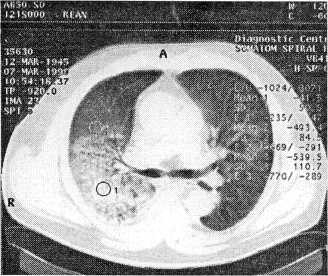

Контрольная РКТ от 07.05.99 г. (рис. 3) после реабилитационной терапии в условиях санатория: в заднебазальных отделах правого легкого определяется участок пневмосклероза; костальная плевра утолщена; левое легкое без патологии.

Рис. 3. Компьютерная томограмма больного В. после излечения и реабилитации

Больной был выписан 3 апреля 1999 г. после лечения в терапевтическом отделении (табл. 4) в удовлетворительном состоянии и прошел реабилитационный период в санаторном учреждении своей климатической зоны. Контрольная РКТ выявила высокую степень рассасывания.